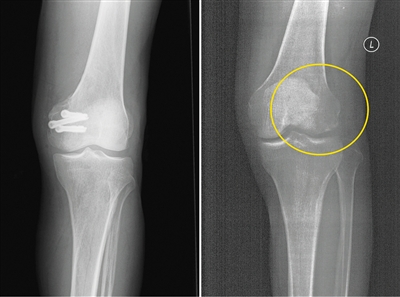

左為使用金屬螺釘后拍攝的影像,右為使用蠶絲螺釘后拍攝的影像。受訪者供圖

在長(zhǎng)期的臨床應(yīng)用過(guò)程中,金屬材料逐漸顯現(xiàn)出三大缺陷:一是金屬內(nèi)固定往往需要二次手術(shù)取出,大大增加了患者的痛苦及經(jīng)濟(jì)負(fù)擔(dān)。二是金屬的力學(xué)強(qiáng)度遠(yuǎn)遠(yuǎn)超過(guò)骨骼,導(dǎo)致應(yīng)力遮擋,影響骨折愈合。此外,使用部分金屬材料術(shù)后無(wú)法進(jìn)行CT和磁共振拍攝;即使鈦合金材料可以進(jìn)行檢查,也存在明顯的偽影,螺釘周邊模糊一團(tuán),嚴(yán)重影響影像觀察的效果。

今年5月,患者張強(qiáng)(化名)不慎扭傷,造成左股骨遠(yuǎn)端骨折。由于骨折部位靠近關(guān)節(jié)面,使用金屬螺釘固定時(shí)應(yīng)力過(guò)大,會(huì)影響骨折愈合;1年后還需要手術(shù)將金屬螺釘取出,可能造成二次創(chuàng)傷。患者入院之后,團(tuán)隊(duì)經(jīng)過(guò)詳細(xì)探討病情、細(xì)致閱片后認(rèn)為,該患者符合可降解蠶絲螺釘固定的適應(yīng)證。術(shù)中團(tuán)隊(duì)對(duì)該患者使用可降解蠶絲螺釘固定骨折塊,術(shù)后的CT片中沒(méi)有任何偽影,可以清晰地看到骨折塊已經(jīng)完全復(fù)位,并且解除了患者二次手術(shù)取出螺釘?shù)呢?fù)擔(dān)和困擾。